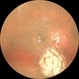

- choroidal coloboma

- Fundus camera

- Pre operative photo of a choroidal coloboma with retinal detachment.